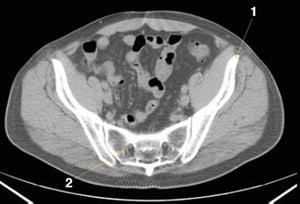

CT-Scan von Abdomen und Becken mit normaler Anatomie ohne Kontrastmittel (Folie 24)

1 = innere iliakale Gefäße; 2 = externe iliakale Gefäße.

© Springer Science+Business Media